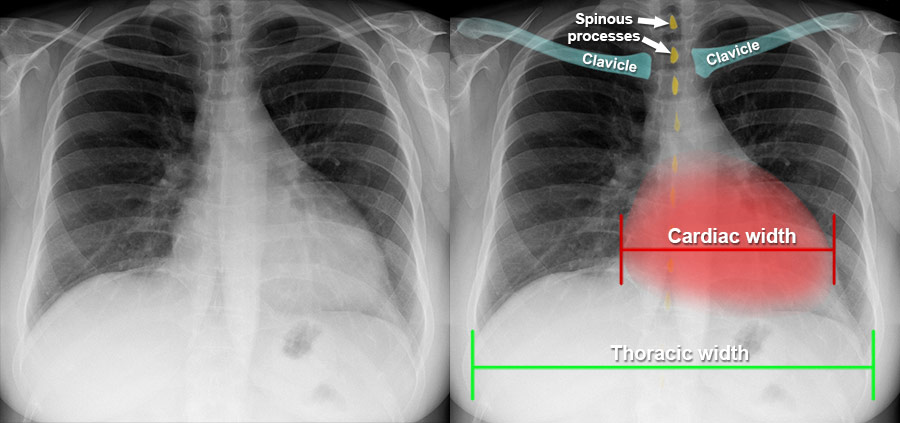

An Electrocardiogram (ECG) indicated ST-segment elevation in leads II, III, and aVF, suggestive of a heart attack. Cardiac Enzyme Studies confirmed myocardial damage with elevated troponin levels, while a Chest X-ray ruled out any lung complications.

Image of Cardiac Arrest Width